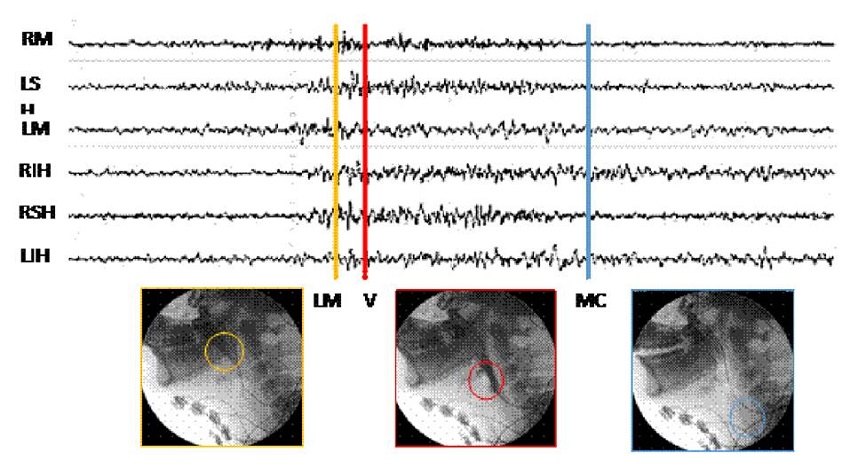

Segmentación de señales

Con ayuda de fonoaudiólogos entrenados en deglución y disfagia, se validó la calidad de cada uno de los videos obtenidos y se determinaron los tiempos en el que el bolo alimenticio inicia la trayectoria en la boca, desciende por la faringe y llega a la porción proximal del esófago. Las imágenes de la videofluoroscopia se utilizaron para detectar tres momentos deglutorios: paso por la línea mandibular, paso por las valleculas epiglóticas y paso por el músculo cricofaríngeo o complejo del esfínter esofágico superior.

Se establecieron marcadores de los tiempos en que sucede cada uno de estos eventos, con el propósito de validar si el paso del alimento por los puntos marcados corresponde a una activación muscular. Bajo visión videofluoroscópica, se posicionaron tres marcadores de eventos sobre una señal electromiográfica multicanal de los seis diferentes grupos musculares evaluados (figura 3).

Se identificó el tiempo en el cual el alimento pasó por la línea mandibular, las valleculas y el músculo cricofaríngeo; y se reconoció el momento en que la señales electromiográficas mostraron inicio y fin de la actividad muscular (onset y offset, respectivamente). Se calcularon las diferencias de tiempo asociadas con: onset y paso por la línea mandibular, onset y paso por las valleculas, offset y paso por la línea mandíbula, y offset y paso por el músculo cricofaríngeo. Además, se calculó la duración del segmento de activación de la señal electromiográfica y la duración de la fase faríngea. Finalmente, se calculó la media de dichos datos con su respectiva desviación estándar, con el fin de evaluar la relación entre los registros de las señales eléctricas y los de los momentos fisiológicos en la videofluoroscopia. El paso del alimento por la línea mandibular se estableció como punto de referencia.